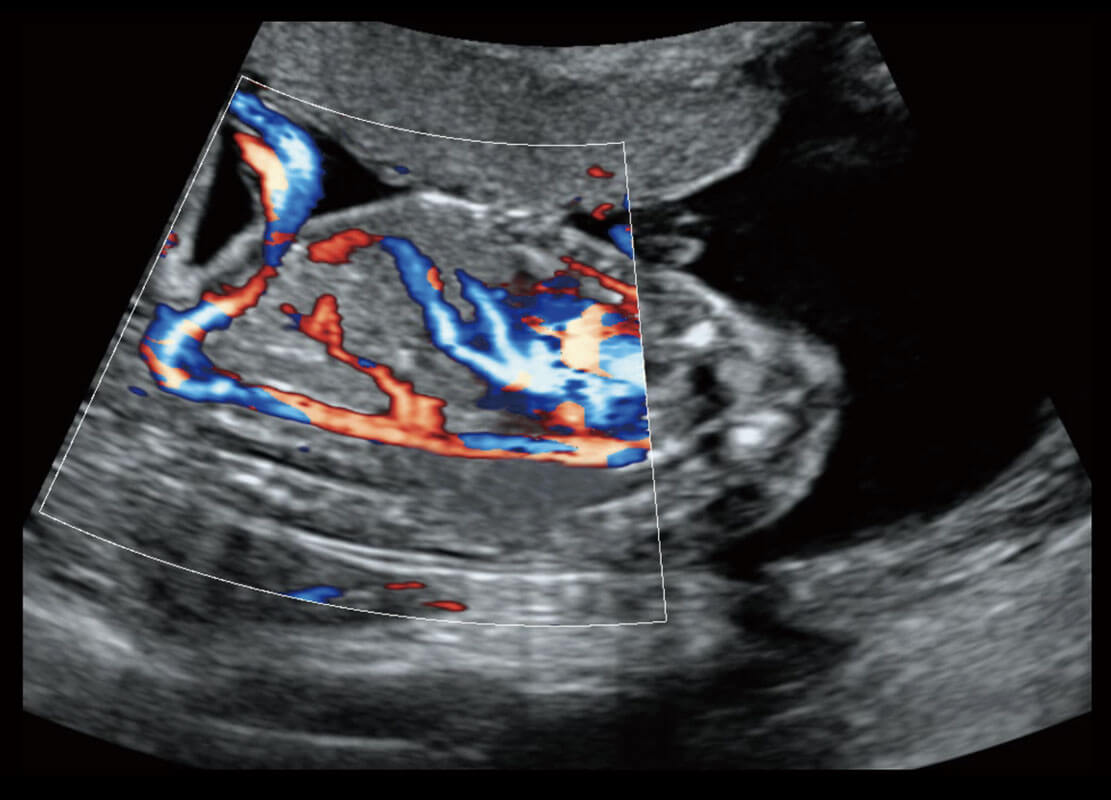

胎心筛查

P60搭载一系列胎儿心脏成像技术,实现更精细的胎儿心脏评估。

• 四腔切面

• 四腔心血流

• 右室双出口

• 胎心容积成像